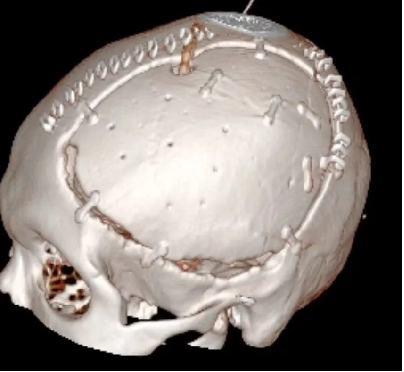

患者术后满三个月再次返院进行颅骨缺损修补术,经过完善术前检查、全科讨论、做好充分手术准备后,武宁县总医院人民医院院区神经外科团队成功为患者完成自体颅骨修补术。

术后: